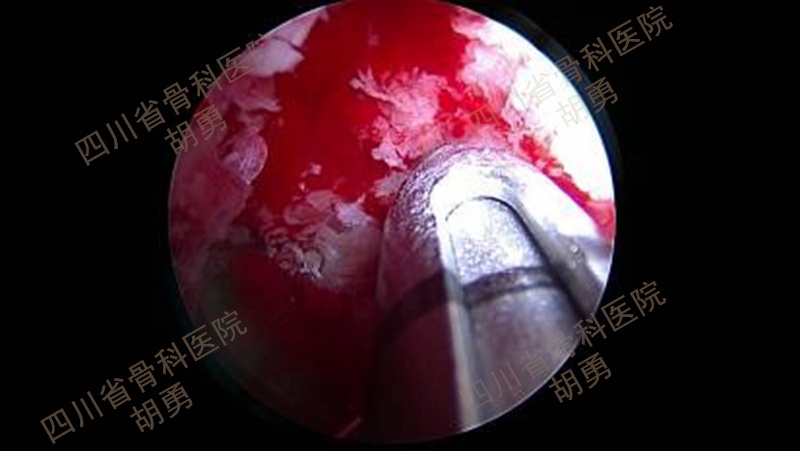

五、镜下清创显露撕脱骨块和骨床

经前下外和前下内入口交替插入关节镜和刨刀,清理、显露撕脱骨块,并将骨块掀起,以显露并新鲜化骨床,如图9所示。对陈旧性撕脱骨折畸形愈合者,还需辨认撕脱骨块之旋转及移位情况,镜下使用小骨刀游离并掀起骨块,使用磨钻新鲜化撕脱骨块和骨床。

图9 清创后镜下显露撕脱骨块及骨床